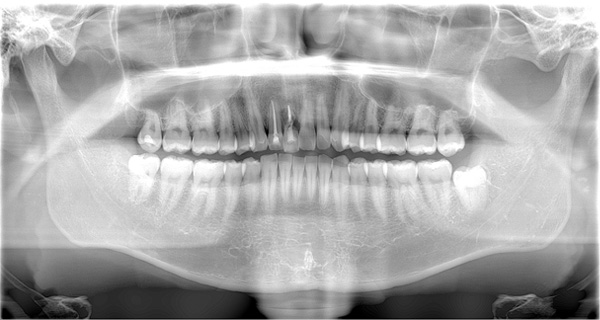

BEFORE

| 年代・性別 | 50代 女性 |

|---|---|

| 主訴 | 左上のブリッジがグラグラして外れそう |

| 治療期間 | 約18ヶ月 |

| 費用 | 1,600,000円 |

| 治療内容 | インプラント、骨造成、サイナスリフト、セラミック修復 |

| 治療に伴うリスク | インプラント周囲炎 セラミックの破折、脱離 |